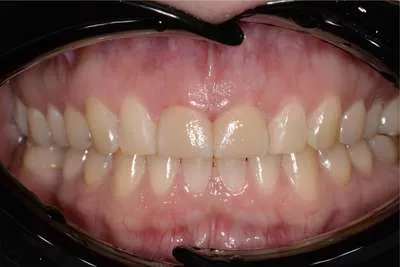

Проблемы, с которыми пациентка обратилась в Dental Way: несостоятельные композитные реставрации, отсутствие 12-го зуба, эстетическая неудовлетворенность зубным рядом, формой, размером зубов.

• Установка имплантата 12 зуба и коронки на него

• Эстетическая реставрация передних зубов с использованием керамических виниров E-max — полностью восстановили эстетику зубного ряда

• Отбеливание зубов по технологии ZOOM 4

После